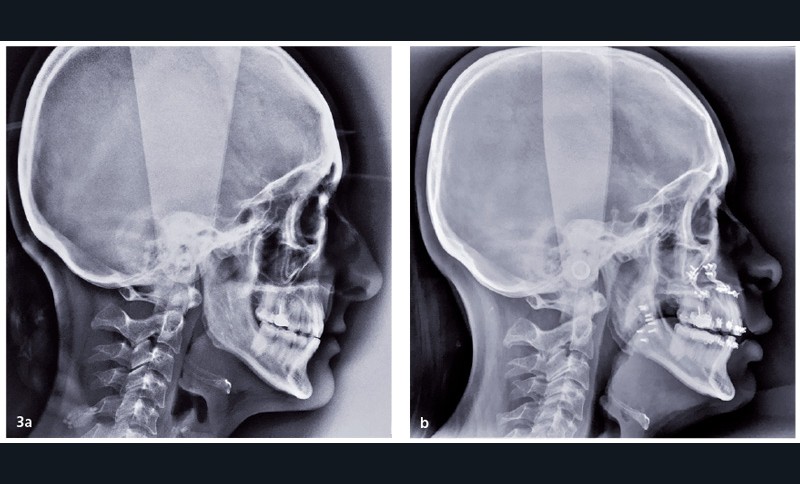

• Une amélioration immédiate des troubles du sommeil et de la qualité de vie des patients porteurs d’un Syndrome d’Apnées Hypopnées Obstructives du Sommeil (SAHOS) liée à l’augmentation des dimensions des voies aérifères supérieures par l’avancée mandibulaire et/ou maxillaire (fig. 3).